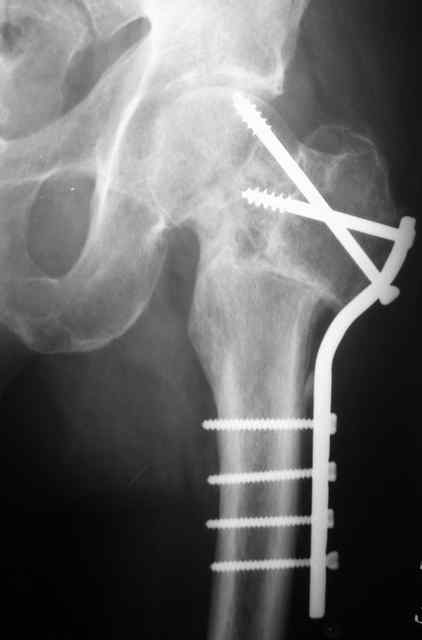

Рентгенография

Если решитесь делать остеосинтез, покажите результат обязательно. Все-таки субкапитальный перелом с вероятным переходом на головку, почти через 3 месяца после травмы. Возможность закрытой репозиции через такой срок вызывает сомнения. Открытая еще больше нарушит кровоснабжение. КТ до операции было бы неплохо сделать.

К сожалению, социальный статус пациента не восстановится ни после остеосинтеза, ни после ТЭП, в армии его уже не оставят. Склоняюсь к варианту медиализирующей остеотомии. С 90-х годов при недоступности основной массе платного эндопротезирования и невозможности три года ожидания квоты пациентам с несросшимися переломами ШБК мы делали вальгирующую чрезвертельную остетомию с медиализацией и пациенты вполне довольны результатами.Осложнения минимальны, начальные аваскулярные дистрофии головки способны к регрессу при соблюдении пациентом режима нагрузки. Очень привлекательно выглядит схема остеотомии с латерализацией удлиняющая шейку, описанная раннее на форуме Д.Кульджановым, но ее пока не выполняли.

Прилагаю снимок пациента 69 лет оперирован лет 8 назад.

Молодой возраст больного является противопоказанием к артропластике, и необходимо сделать все возможное, чтобы уйти от "внутренней ампутации" головки. С момента травмы более трех месяцев, и жизнеспособность головки пока не вызывает опасений. Свободная подвиженность по линии перелома доказывает, что патология в стадии ложного сустава.

Из предложенных методов вальгусная остеотомия создает наилучшие биомеханические условия. Успех более 92%, делается внесуставно с наименьшим риском для кровоснабжения. Межвертельная остеотомия около 20-25 градусов и стандартная фиксация 120 градусным Blade Plate.